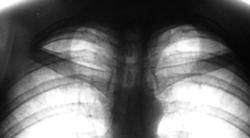

Пол пациента: Мужской пол Тип патологии: Другое Область исследования: Грудная клетка и верхние дыхательные пути Методы исследования: Rg "Флюшка". Какие мнения будут уважаемые коллеги? https://radiomed.ru/sites/default/files/styles/case_slider_image/public/user/12/2.dscn0130.jpg?itok=k6YaQ-2w https://radiomed.ru/sites/default/files/styles/case_slider_image/public/user/12/3.dscn0130a.jpg?itok=j8kO8Dop ID:23365 Чт, 27/09/2012 - 15:00 #1 Nikolas Не на сайте Был на сайте: 1 месяц 4 недели назад Зарегистрирован: 21.12.2010 - 20:37 Публикации: 4559 туберкулез легких. В ПТД. Обязательно выполнить томографию легких. Чт, 27/09/2012 - 15:11 #2 Катенёв Валенти... Не на сайте Был на сайте: 7 лет 3 недели назад Зарегистрирован: 22.03.2008 - 22:15 Публикации: 54876 Это опять к нашему фтизиатру надо его направить? Чт, 27/09/2012 - 16:50 #3 Nikolas Не на сайте Был на сайте: 1 месяц 4 недели назад Зарегистрирован: 21.12.2010 - 20:37 Публикации: 4559 направить. Не первый раз Вы показывали прогрессирование процесса при отсутствии своевременного исследования. С уважением Nikolas Чт, 27/09/2012 - 17:01 #4 Катенёв Валенти... Не на сайте Был на сайте: 7 лет 3 недели назад Зарегистрирован: 22.03.2008 - 22:15 Публикации: 54876 Мы разрезали...Приложения: Чт, 27/09/2012 - 22:15 #5 Гриша Хата Не на сайте Был на сайте: 10 лет 1 неделя назад Зарегистрирован: 09.02.2011 - 20:40 Публикации: 665 Неоднократно встречал склероз на верхушках под уплотнённой апикальной плеврой, который не прогрессировал на протяжении многих лет. Чт, 27/09/2012 - 22:52 #6 И.Бондаренко Не на сайте Был на сайте: 1 день 10 часов назад Зарегистрирован: 13.09.2011 - 22:55 Публикации: 9206 По мне, инфильтрация 1 сегментов в верхушках. Чт, 27/09/2012 - 22:58 #7 Гриша Хата Не на сайте Был на сайте: 10 лет 1 неделя назад Зарегистрирован: 09.02.2011 - 20:40 Публикации: 665 А по-мне, грудинные концы ключиц размазались. Чт, 27/09/2012 - 23:02 #8 Катенёв Валенти... Не на сайте Был на сайте: 7 лет 3 недели назад Зарегистрирован: 22.03.2008 - 22:15 Публикации: 54876 Гриша Хата wrote: А по-мне, грудинные концы ключиц размазались. Срезы - 7, 8, 9, 10 см. от спины. На мой взгляд, ключицы по отношению к этим срезам в заооблачной высоте. Чт, 27/09/2012 - 23:35 #9 Гриша Хата Не на сайте Был на сайте: 10 лет 1 неделя назад Зарегистрирован: 09.02.2011 - 20:40 Публикации: 665 Во-первых, на обзорной рентгенограмме нет признаков инфильтрации. Во-вторых, "инфильтрация" появляется на томограммах вместе с тенями ключиц. В-третьих, ключицы потому так сильно размазались, что находятся далеко не в срезе. Пт, 28/09/2012 - 01:12 #10 Петрович Не на сайте Был на сайте: 7 лет 2 месяцев назад Зарегистрирован: 22.03.2009 - 01:13 Публикации: 3908 Как непривычны-неудобны позитивы для лёгких. Мне кажется, здесь при наиболее вероятной патологии S1 с двух сторон, трудно исключить и патологию верхнего средостения. Вот бы ещё срезов кпереди… Неоднозначно всё Сб, 29/09/2012 - 12:33 #11 Катенёв Валенти... Не на сайте Был на сайте: 7 лет 3 недели назад Зарегистрирован: 22.03.2008 - 22:15 Публикации: 54876 Петрович wrote: Как непривычны-неудобны позитивы для лёгких. Мне кажется, здесь при наиболее вероятной патологии S1 с двух сторон, трудно исключить и патологию верхнего средостения. Вот бы ещё срезов кпереди… Делали еще кпереди, но на 11 и 12 см. было хуже видно, на 12 см. почти ничего.

туберкулез легких. В ПТД. Обязательно выполнить томографию легких.

По мне, инфильтрация 1 сегментов в верхушках.

А по-мне, грудинные концы ключиц размазались.

Срезы - 7, 8, 9, 10 см. от спины. На мой взгляд, ключицы по отношению к этим срезам в заооблачной высоте.

Во-первых, на обзорной рентгенограмме нет признаков инфильтрации.

Во-вторых, "инфильтрация" появляется на томограммах вместе с тенями ключиц.

В-третьих, ключицы потому так сильно размазались, что находятся далеко не в срезе.

Мне кажется, здесь при наиболее вероятной патологии S1 с двух сторон, трудно исключить и патологию верхнего средостения. Вот бы ещё срезов кпереди…

Делали еще кпереди, но на 11 и 12 см. было хуже видно, на 12 см. почти ничего.